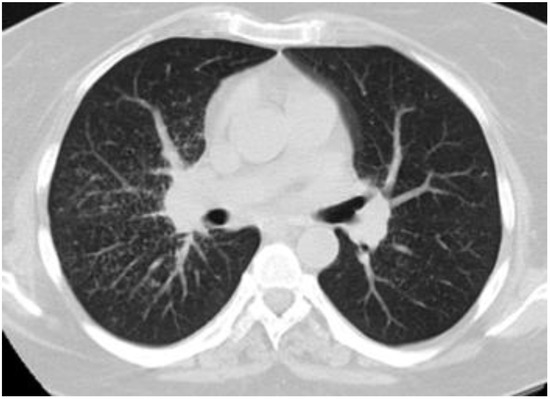

Figure 4.

Sarcoid-like pattern in a 45-year-old female with PBC-AIH overlap.